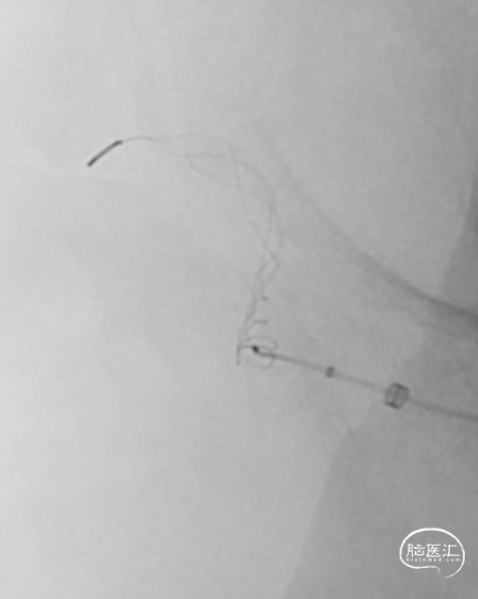

以8F导引导管做支撑送入右侧颈内C1段,同轴送入132cm-AXS Catalyst-6中间导管、150cm-0.021-Trevo Pro 18微导管、200cm-0.014-Synchro2微导丝;CAT-6送至M1段闭塞处;微导管送入右侧大脑中动脉M2段后,1ml注射器回抽见血液回流再手动造影。

选用4mm×20mm-Trevo Provue取栓支架,将有效段远端放置于大脑后动脉开口处,后退微导管释放支架,见支架尾端存在可疑的释放不全感,提示可能的血栓/狭窄。静待5分钟使支架与血栓镶嵌更紧密。

仅将支架末端无效段拉至CAT-6里面,CAT-6的Y阀处连接50ml注射器负压持续抽吸,同时将中间导管及支架拉出体外,见一35mm×2mm长条血栓附着于支架上,随后20ml注射器于长鞘内再次抽吸,可见顺畅血流进入注射器。